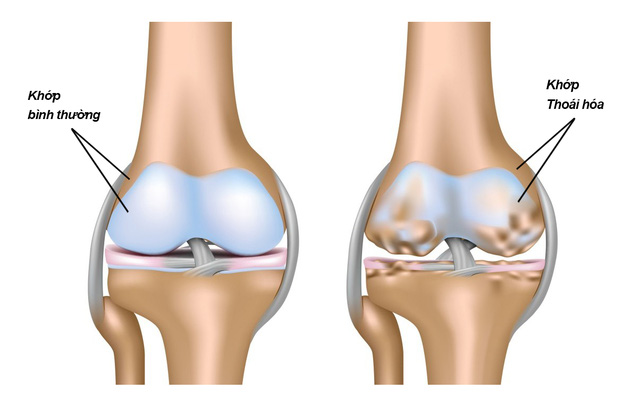

Viêm khớp dạng thấp, loãng xương, một số bệnh khớp khác đều gây ra thoái hóa khớp, làm cho các tổ chức sụn bị hư hỏng, các chất bôi trơn khớp sụt giảm về số lượng, độ nhớt, khớp bị cứng khô gây đau đớn, vận động khớp (đi lại, đứng lên ngồi xuống, lao động) khó khăn, phát ra tiếng kêu lạo xạo. Thuốc điều trị thoái hóa khớp có chức năng tạo ra các tổ chức sụn, hoạt dịch và bảo vệ các tổ chức này. Có nhiều thuốc được nghiên cứu nhưng chỉ có ba chất chính glucosamin, chondroitin, hyaluronat, được FDA, EMA công nhận có đầy đủ các chức năng này.